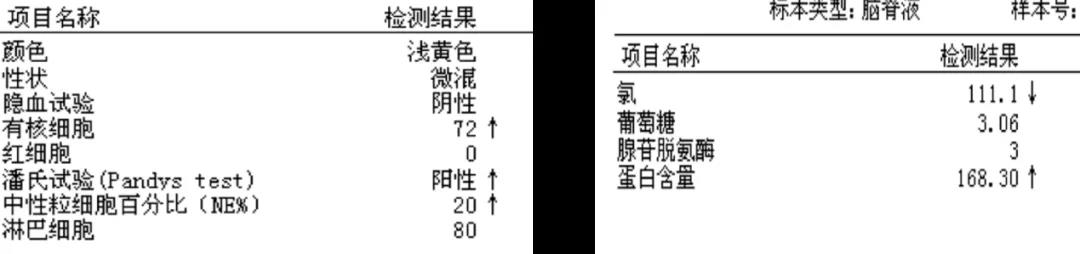

3月25日腰椎穿刺:脑脊液淡黄色清亮,测压220 mmH₂O。脑脊液常规及生化如图9,培养及涂片均为阴性。

图9. 3月25日脑脊液常规及生化结果